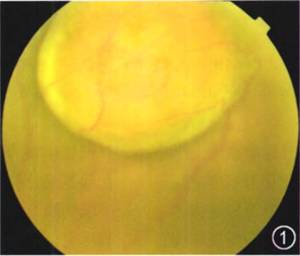

眼科检查:视力:右眼0.02,左眼1.0,眼压:右眼10 mmHg(1 mmHg=O.133 kPa),左眼14 mmHg,右眼前节未见明显异常,玻璃体混浊,视鼻上方可见一蘑菇样粉红色肿物,无色素,表面光滑,可见血管爬行,黄斑区中心凹反光不清(图1)。左眼未见明显异常。

图1 右眼视力下降患者右眼彩色眼底照相